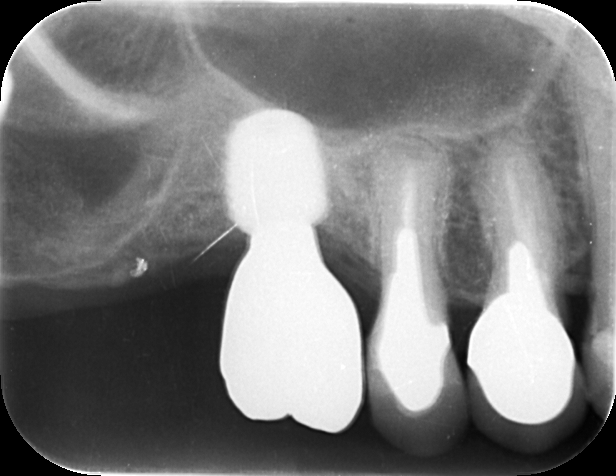

太くて短いインプラントの周りにしっかりと骨が再生されているのが分かりますね。

インプラントの先端はしっかり鼻の空洞(上顎洞と言います)の唯一固い底の骨にがっちり食い込んでいます。(この先端の位置決めが短かい骨でもインプラントを可能にします)